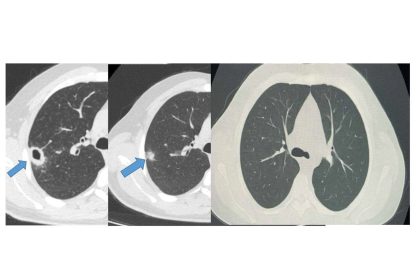

Bayburt’ta 50 yaşındaki hasta erken tanıyla sağlığına kavuştu

Bayburt Devlet Hastanesine öksürük ve balgam şikayetiyle başvuran 50 yaşındaki hastanın akciğerinde…